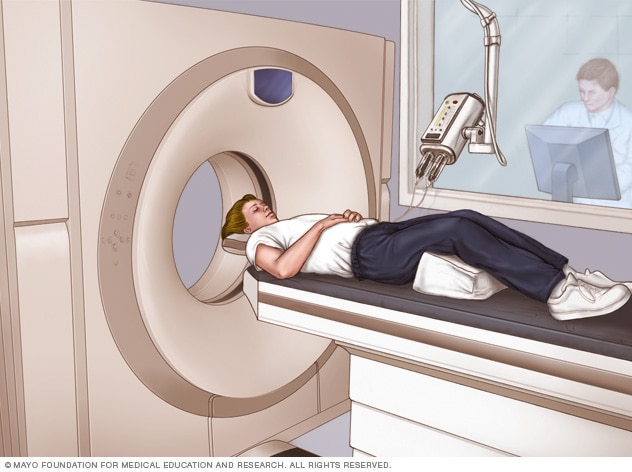

CT scanner

A CT scan can show nearly all parts of the body. Healthcare professionals use it to diagnose disease or injury and to plan medical, surgical or radiation treatment.

- Computerized tomography (CT) scan. A CT scan uses X-rays to obtain cross-sectional images of your brain. CT scans can detect tumors, bleeding or cysts in the brain that might be causing epilepsy.

- Magnetic resonance imaging (MRI). An MRI uses powerful magnets and radio waves to create a detailed view of the brain. Like a CT scan, an MRI looks at the structure of the brain to detect what may be causing seizures. But an MRI provides a more detailed look at the brain than a CT scan.

- Functional MRI (fMRI). A functional MRI measures the changes in blood flow that occur when specific parts of the brain are working. This test may be used before surgery to identify the exact locations of critical functions, such as speech and movement. This allows surgeons to avoid those areas while operating.